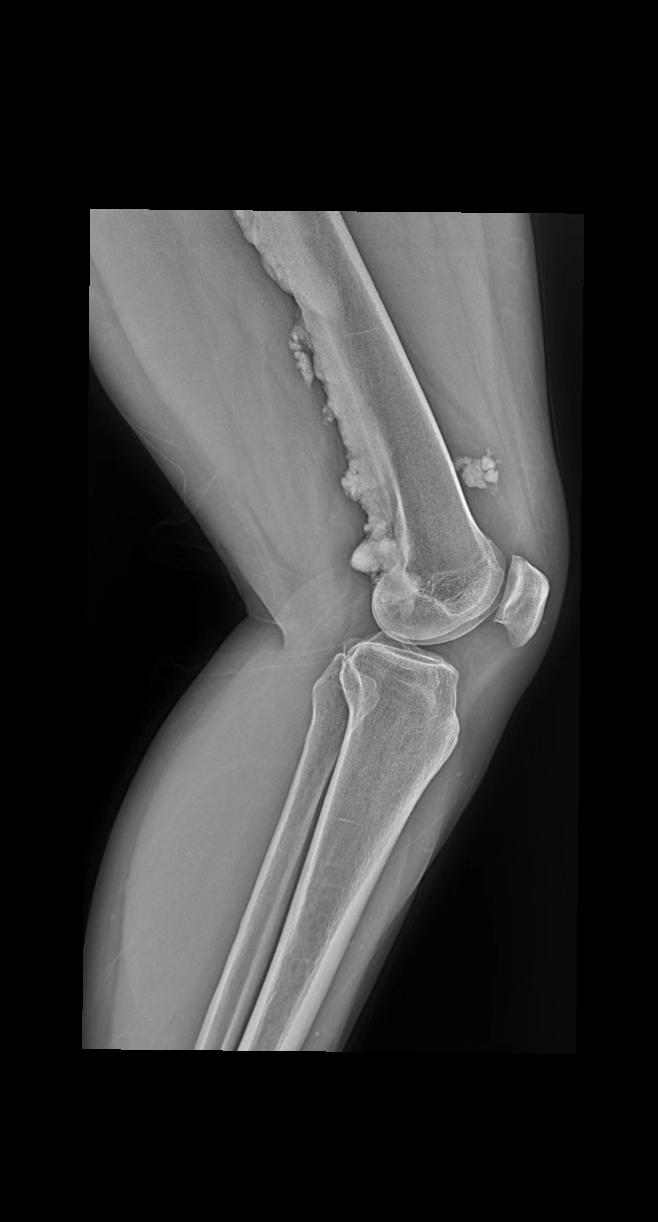

女 55 左侧关节疼痛